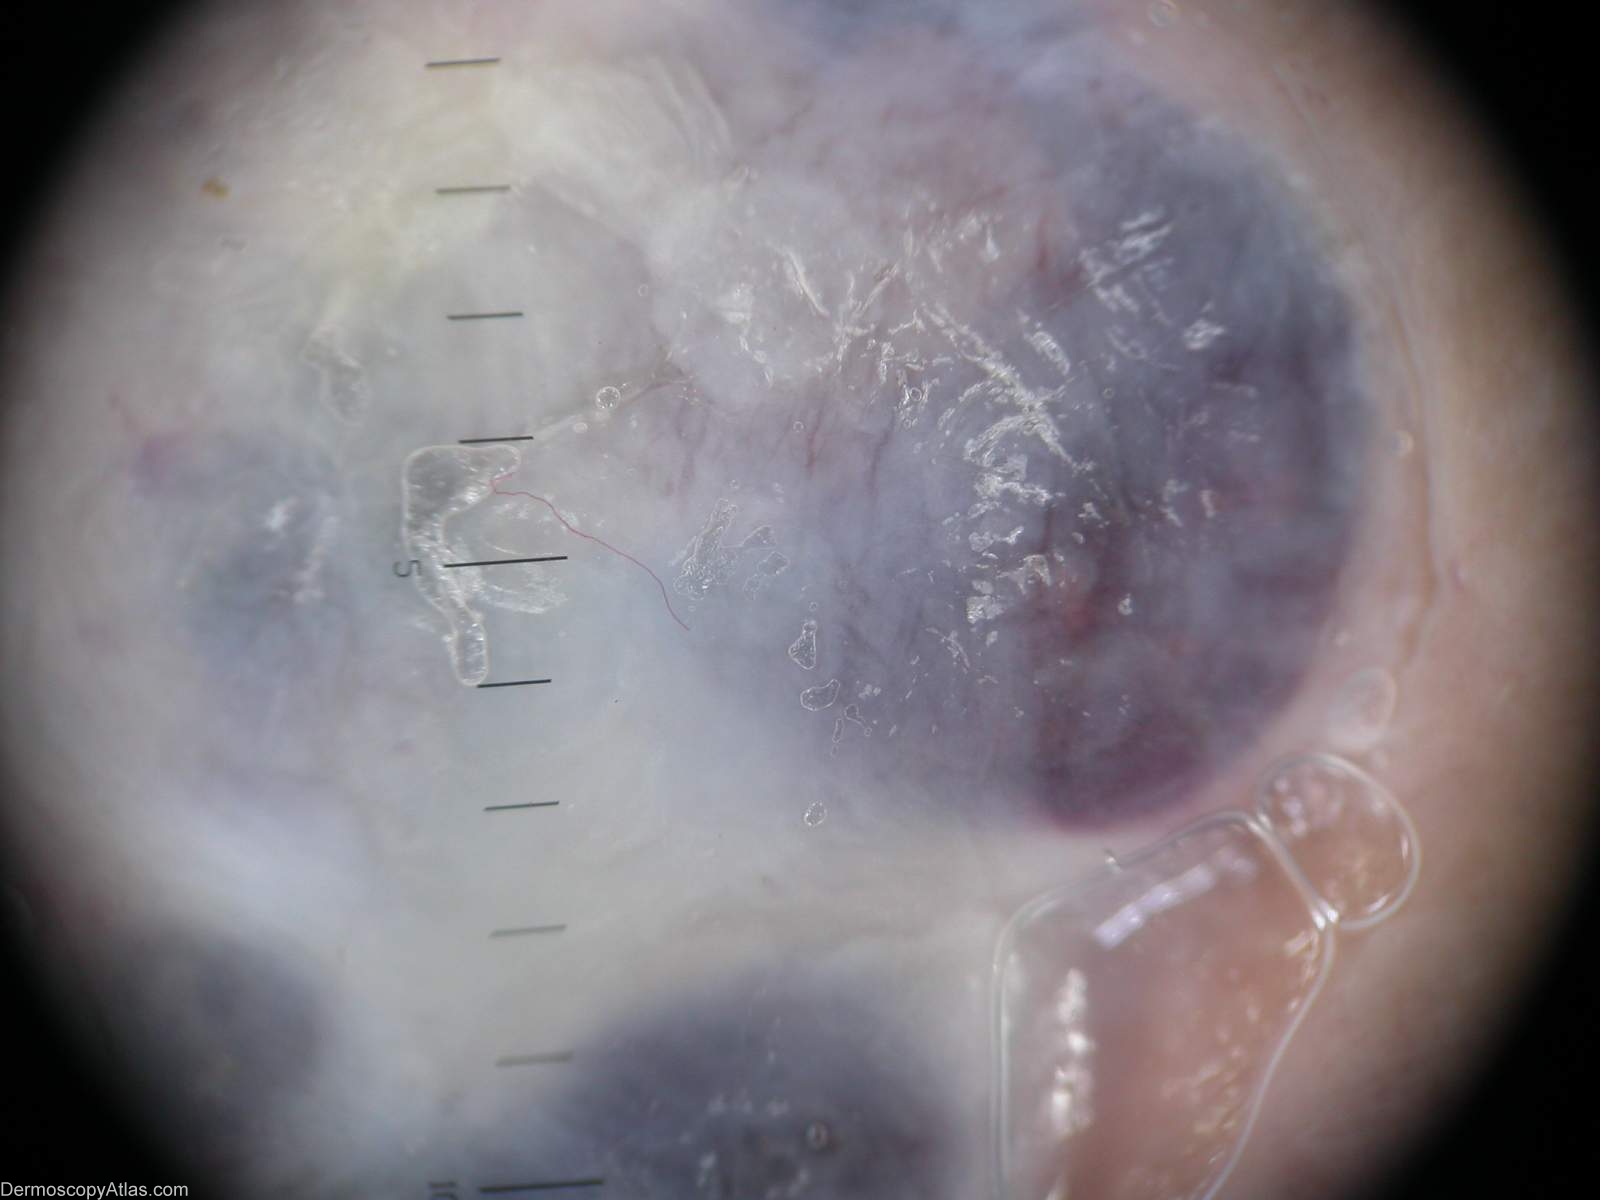

Diagnosis - Pigmented basal cell carcinoma

Diagnosis: Pigmented basal cell carcinoma